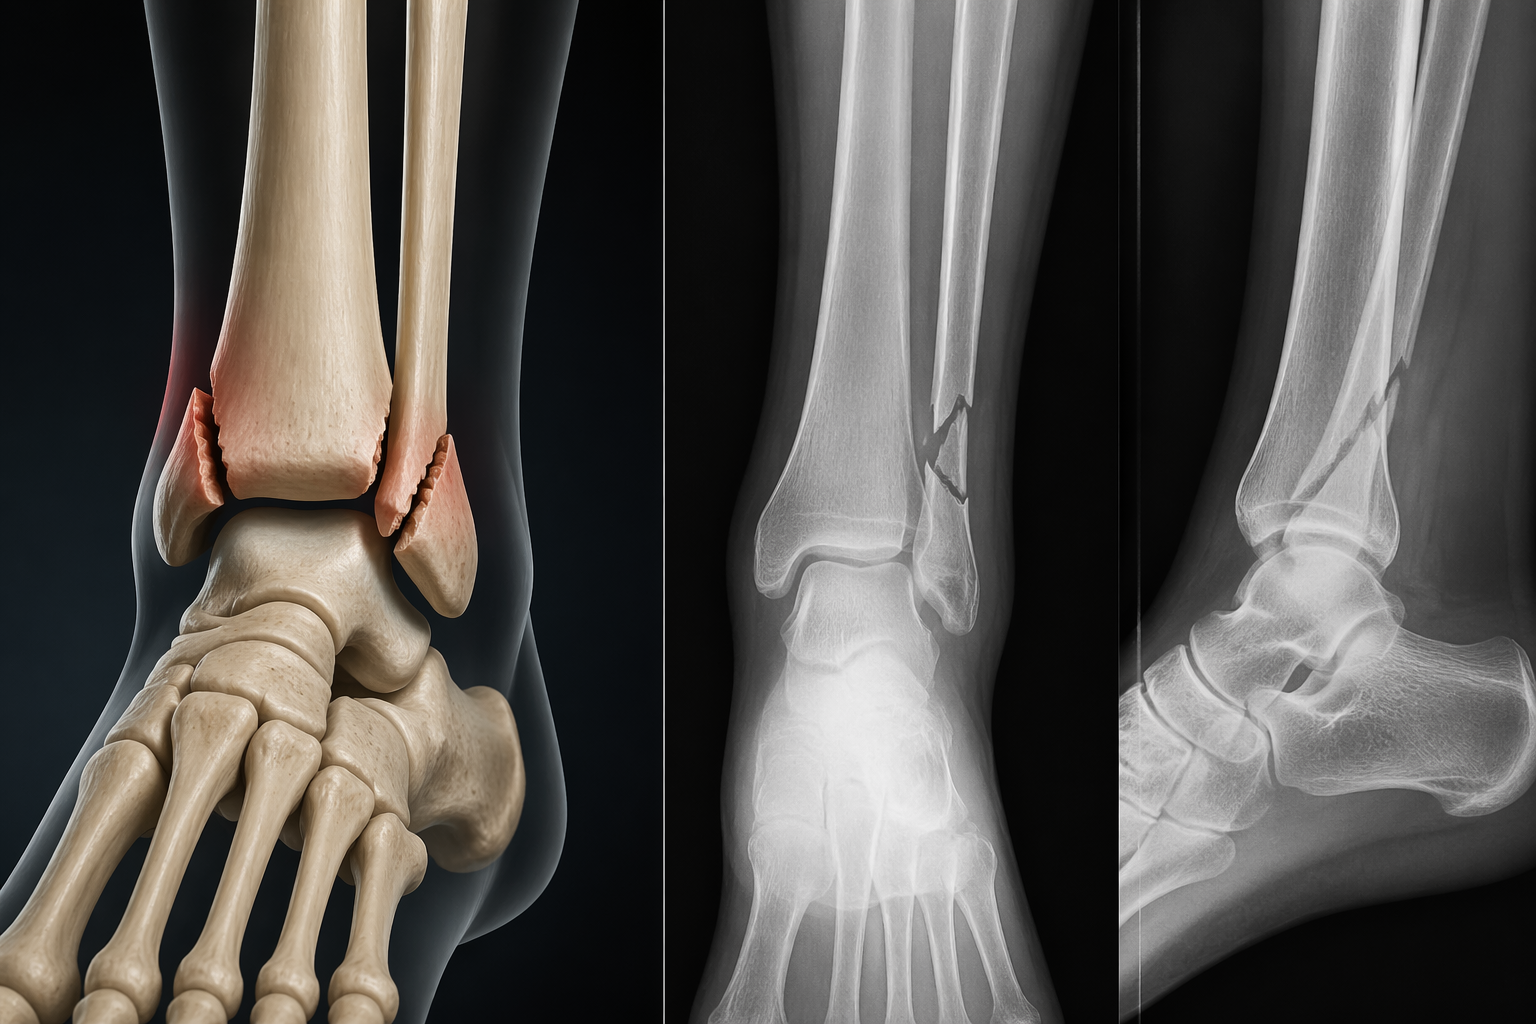

Menisküs yırtığı, menisküs dokusunun kısmen veya tamamen yırtılması sonucunda meydana gelir. Bu durum genellikle diz ekleminin ani şekilde dönmesi veya zorlanması sonucu ortaya çıkar.

Menisküs yırtıkları spor aktiviteleri sırasında sık görülse de bazı durumlarda basit bir hareket bile menisküs yırtığına neden olabilir. Özellikle yaş ilerledikçe menisküs dokusu zayıflar ve daha kolay yırtılabilir.

Op. Dr. Hilmi Karadeniz, menisküs yırtıklarının çoğunlukla ani hareketler ve diz eklemine aşırı yük binmesi sonucu oluştuğunu belirtmektedir.

Travmalar ve Kazalar

Diz üzerine alınan darbeler veya trafik kazaları da menisküs yırtığına yol açabilir. Özellikle diz ekleminin zorlanmasına neden olan travmalar menisküs dokusunun zarar görmesine neden olabilir.

Spor yaralanmaları dışında günlük yaşamda meydana gelen düşmeler de menisküs yırtıklarına yol açabilir.

Op. Dr. Hilmi Karadeniz, diz üzerine alınan ciddi darbelerin menisküs ve bağ yapılarında hasara neden olabileceğini ifade etmektedir.